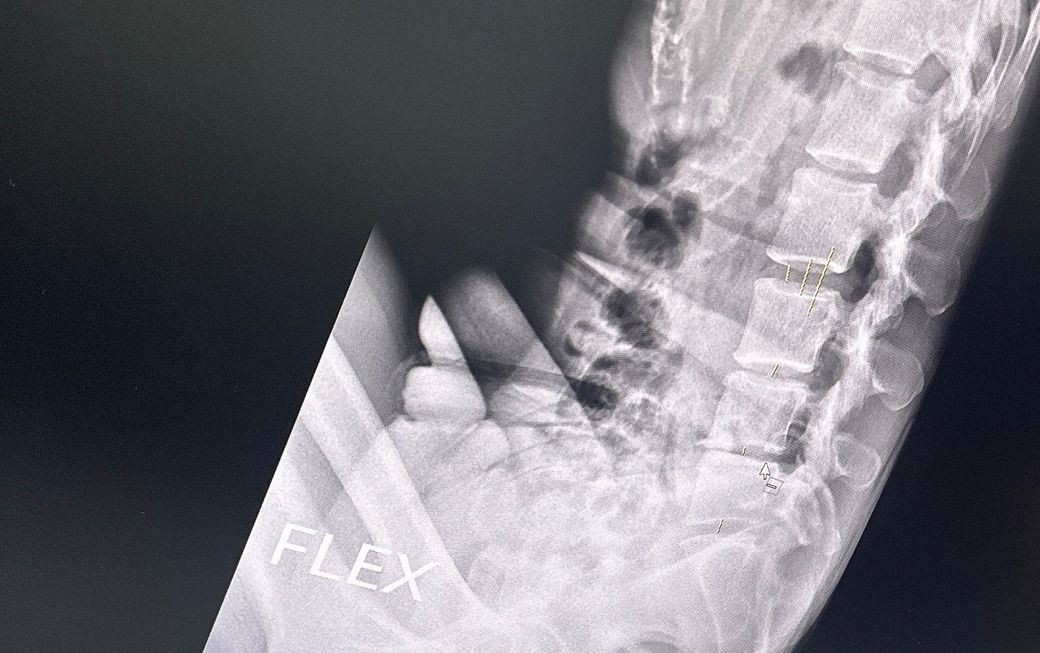

4번5번이 너무 가까워져 있어요

• 1번 째 사진